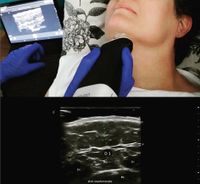

Ecografía cutánea

Ecografía Estética y Dermatológica:

Galería de imágenes